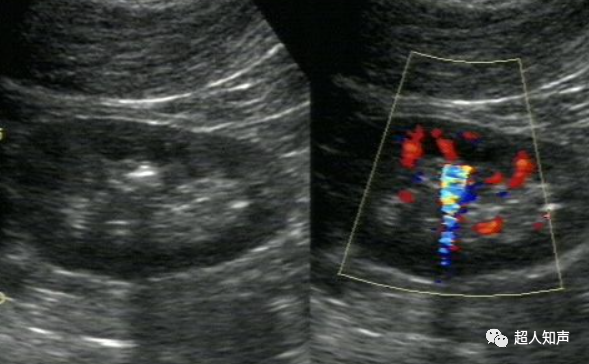

(二)、彩色混叠及彩色血流信号“外溢”伪像

1.彩色混叠

利用脉冲多普勒测量血流速度,受脉冲重复频率(PRF) 的限制,当超过尼奎斯特(Nyquist)频率极限时,就会产生血流方向的倒错表达,出现混叠伪像。操作中将彩标范围调节过低,即过分降低了脉冲重复频率,可以人为造成混叠,出现假性湍流。此时应注意调节彩标范围,可使这种“假性湍流”消失。